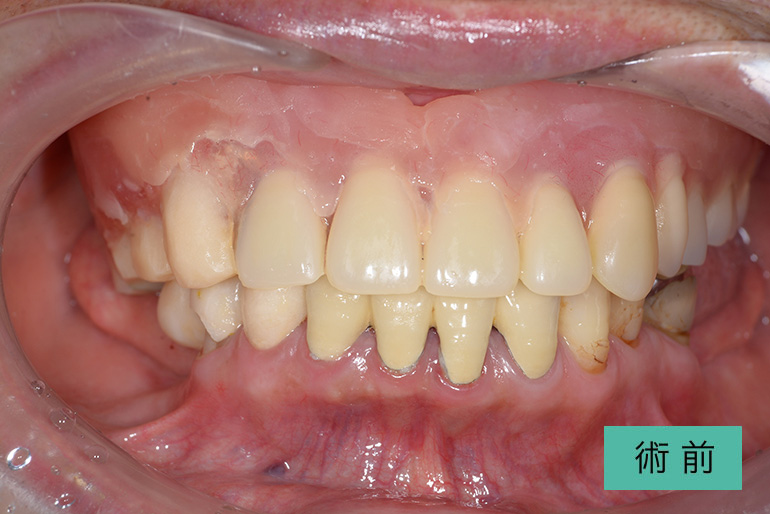

オールセラミック②

| 治療内容 | 上顎前歯右上3番から左上3番のセラミック冠 |

| 治療期間・回数 | 約1ヶ月、3回 |

| 費用(税込) | ¥990,000(165,000/1本)(補綴費用) ※自由診療 |

| リスク・副作用 | 疼痛、補綴物の脱落、咬合違和感、破折 |